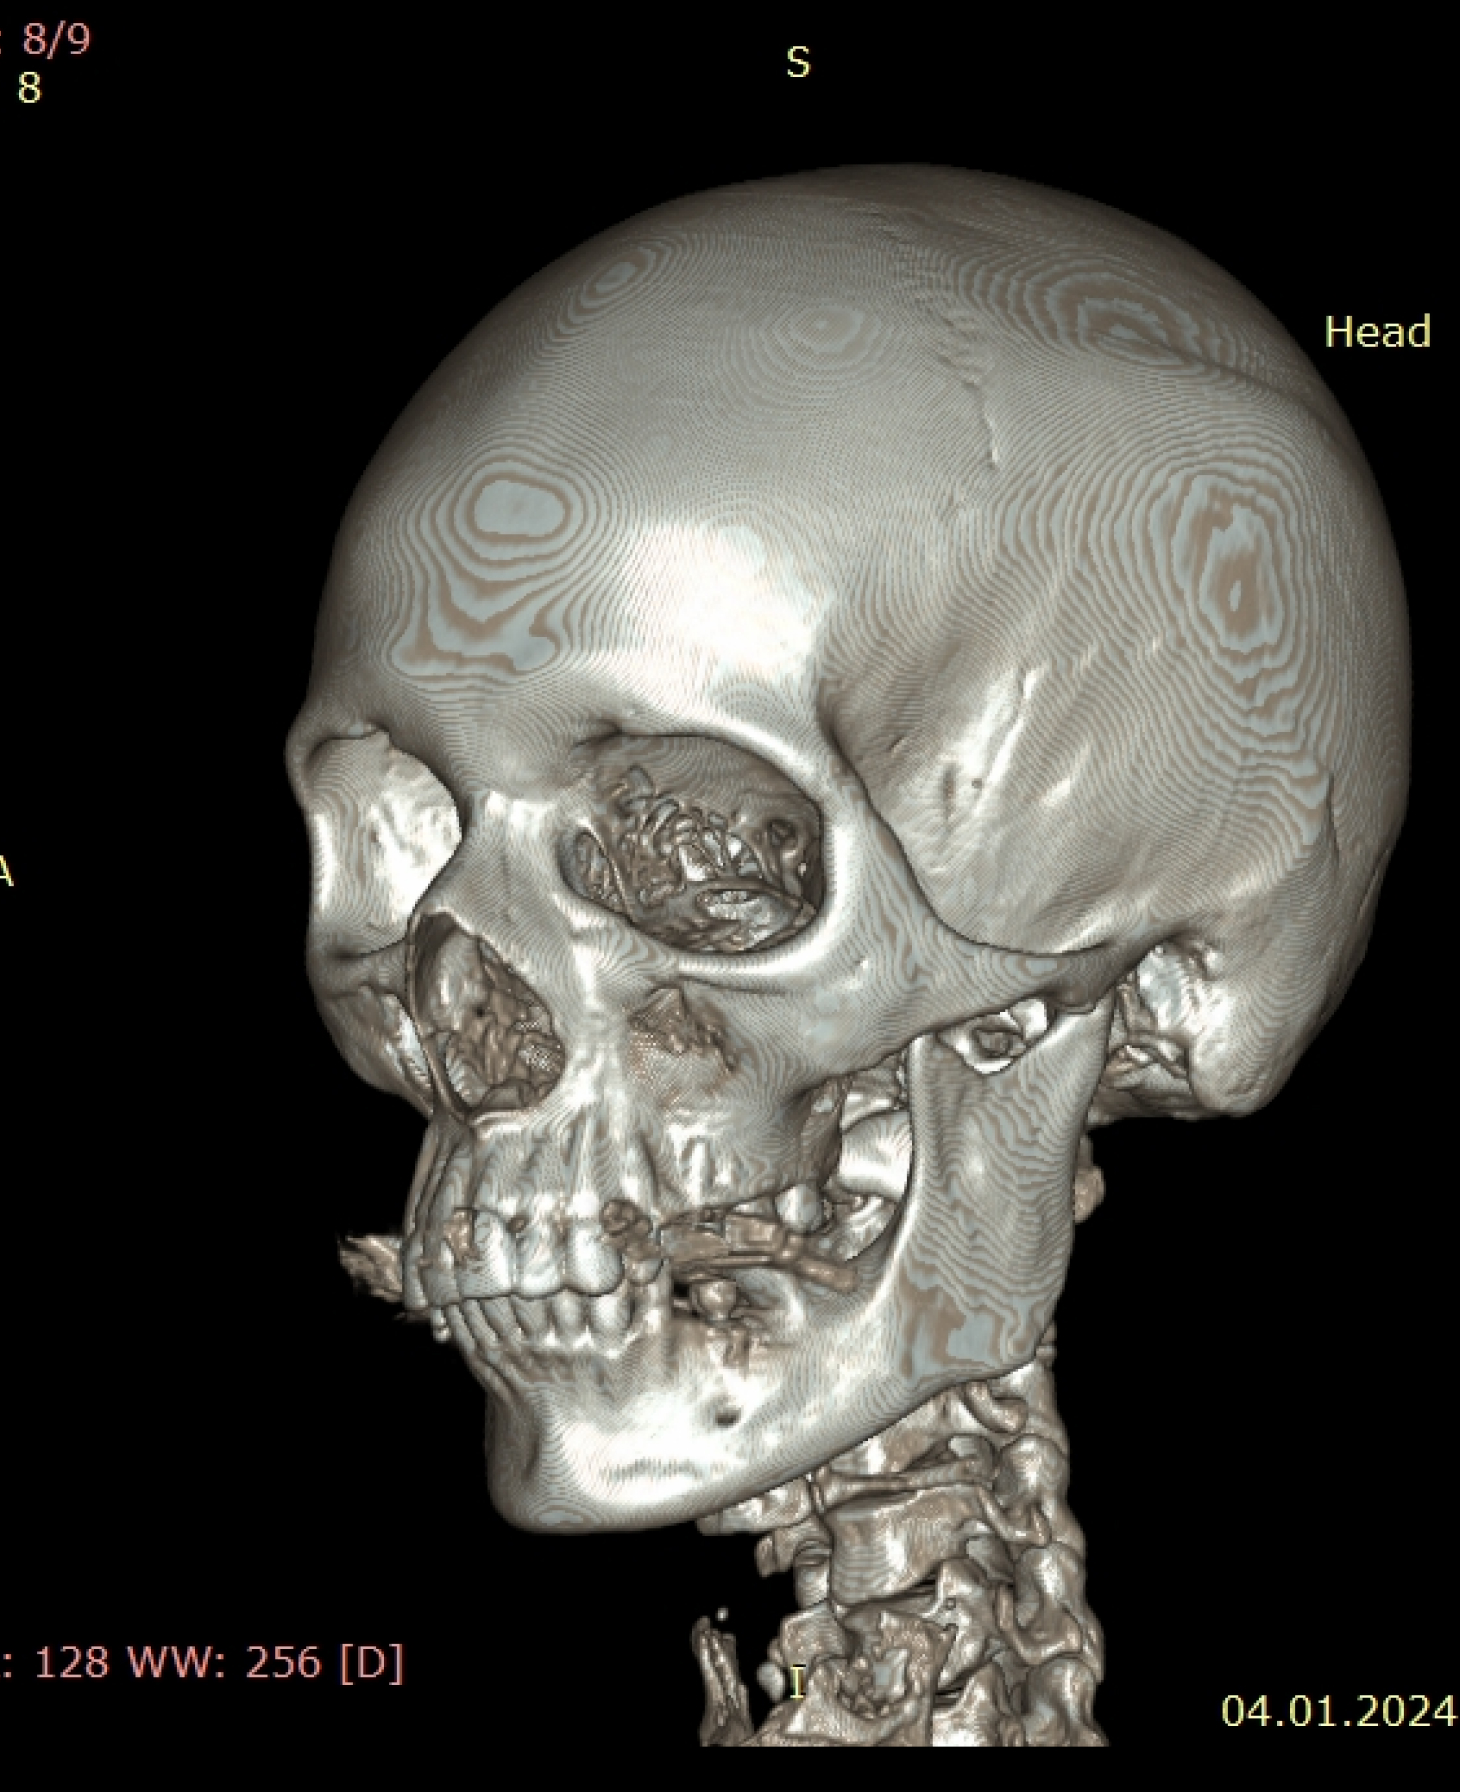

Мультиспиральный томограф выполняет послойное сканирование области верхней и нижней челюстей с помощью рентгеновских лучей, а затем, используя компьютерную обработку данных, создает 3D-модели исследуемой зоны. Современные модели томографов проводят круговое сканирование по спирали, делая срезовые снимки на расстоянии 0,5 мм друг от друга. Затем на основе этих данных реконструируются детальные изображения челюстно-лицевой области в трехмерном формате.

- Информативность. Дентальная КТ позволяет обнаружить признаки патологии, которые не видны на обычных (2D) панорамных снимках – ортопантомограммах. На двухмерных рентгенограммах различные структуры накладываются друг на друга. В отличие от этого пространственные модели дают возможность рассмотреть челюстно-лицевой аппарат в различной проекции и плоскости.

- Широкие возможности диагностики. На трехмерных изображениях можно увидеть в целом верхнюю и нижнюю челюсть, включая гайморовы пазухи, височно-нижнечелюстные суставы. Помимо костной ткани при проведении КТ можно оценить состояние окружающих мягких тканей. Это бывает особенно важно при выборе оптимального способа протезирования и имплантации, при подозрении на опухолевые процессы, при планировании оперативного вмешательства.